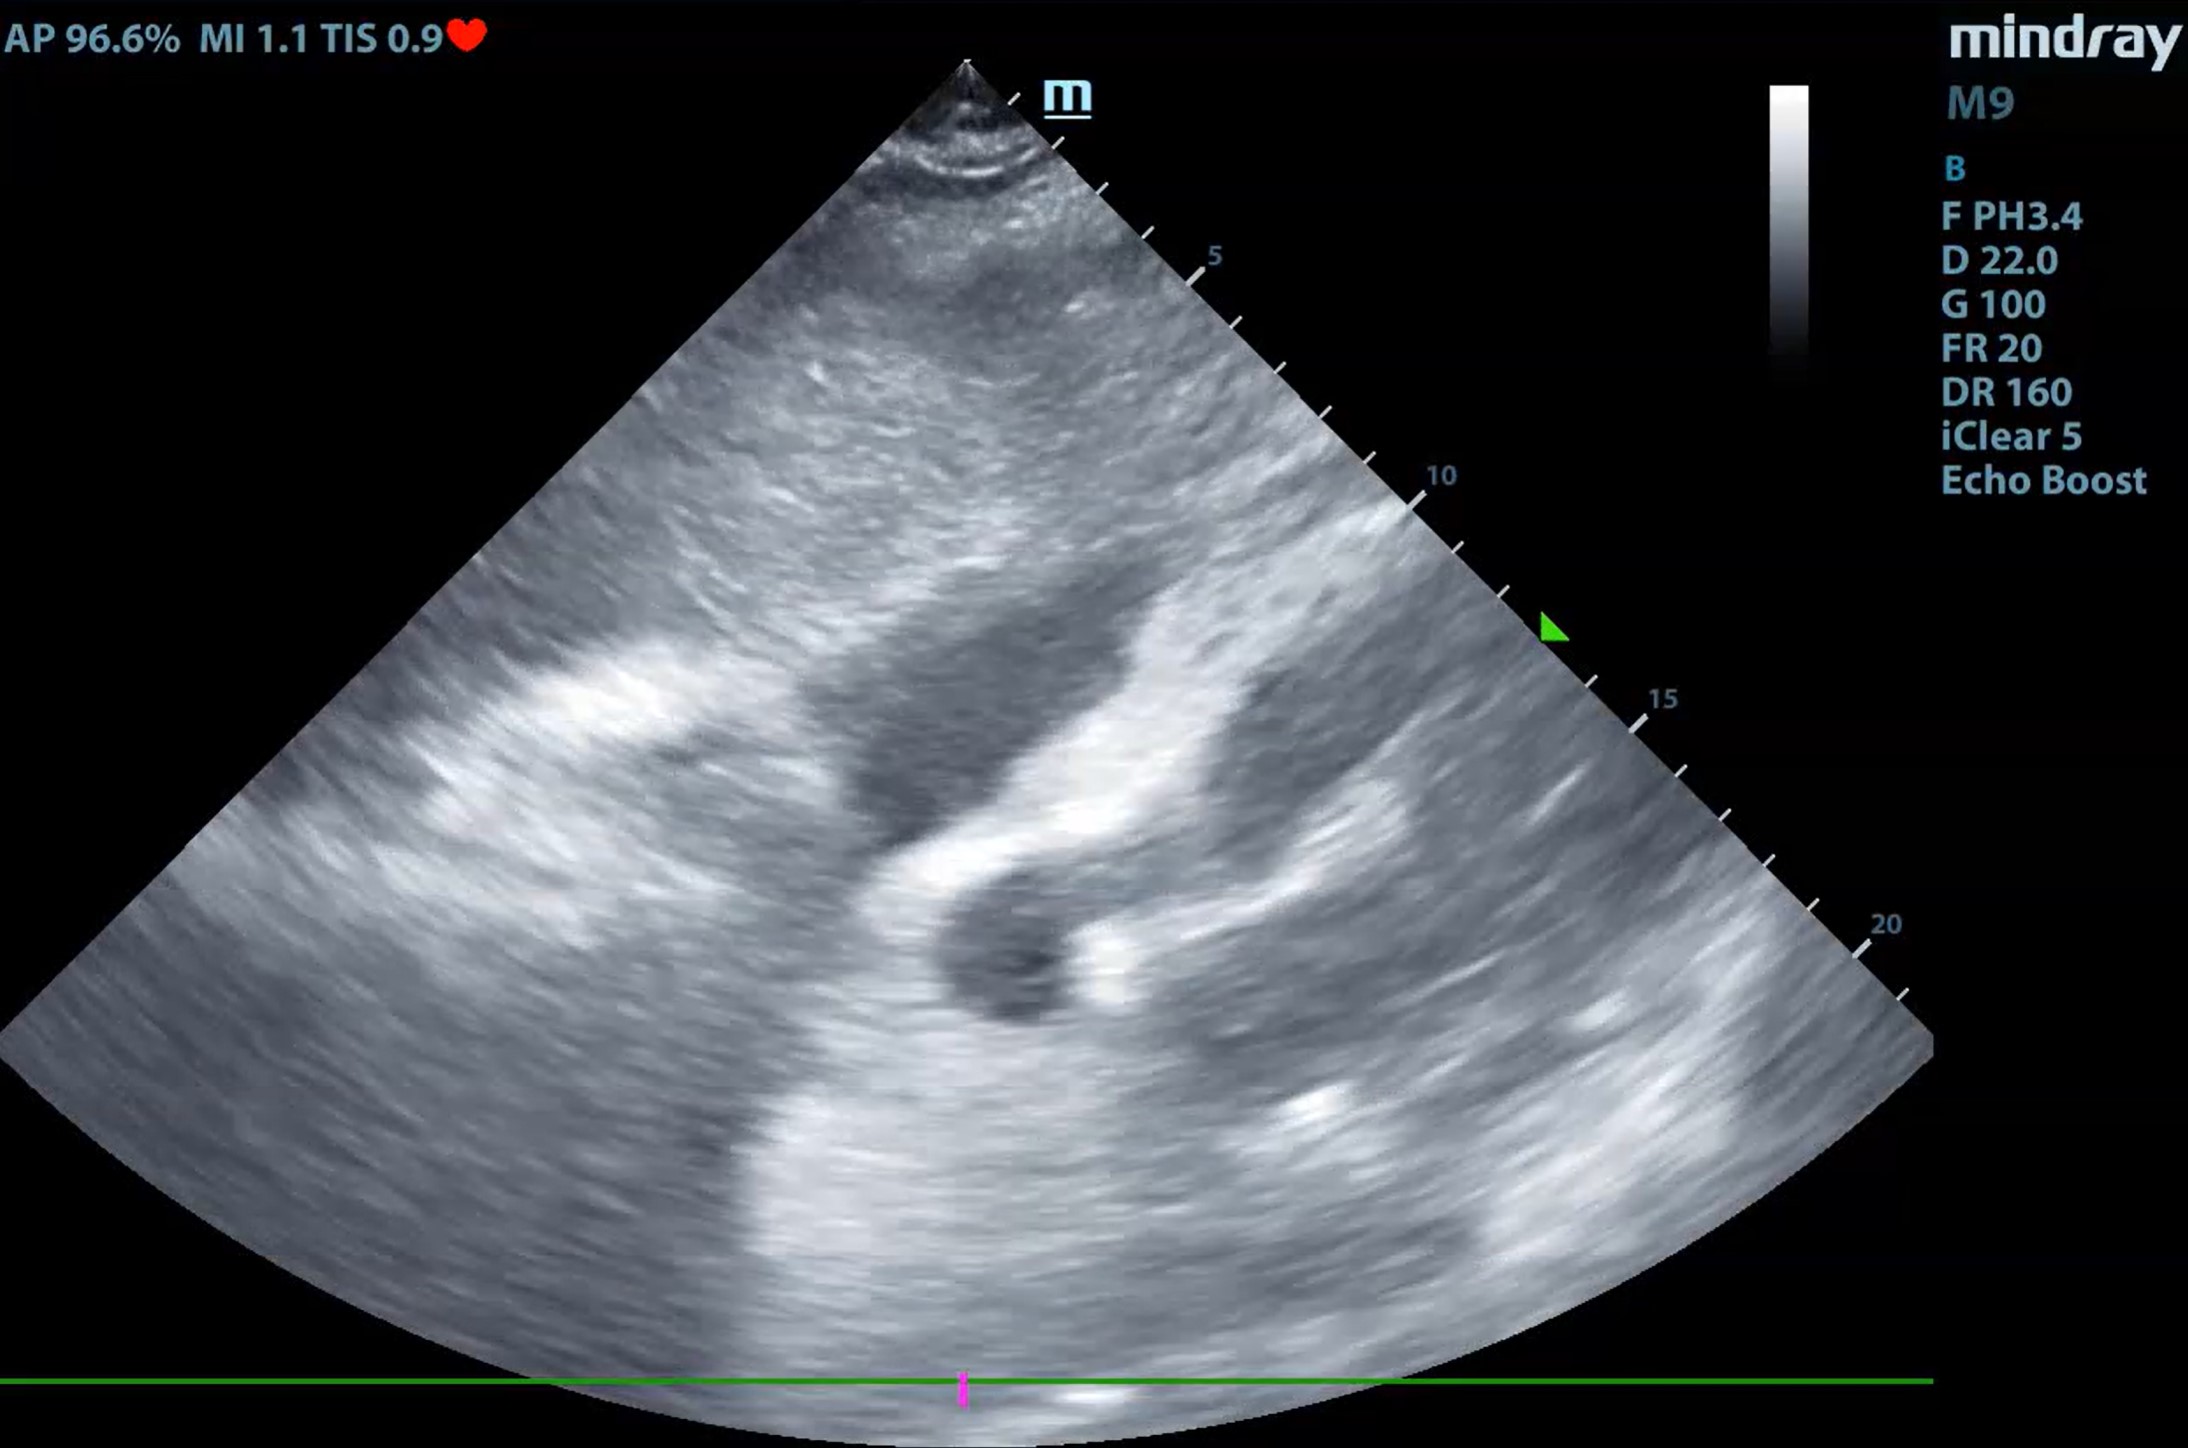

A través de una serie de casos clínicos surgidos tanto en la consulta como en los domicilios, hemos llevado a cabo una revisión de cómo aplicar la ecografía clínica para mejorar el diagnóstico diferencial del paciente con disnea y su posterior seguimiento. Tras la realización de dicha revisión bibliográfica nos reunimos los responsables de ecografía del centro de salud para realizar una serie de sesiones clínica y compartir nuestra experiencia y plantear un algoritmo sencillo de aplicar en nuestra práctica diaria.

La disnea es una sensación subjetiva de dificultad para respirar siendo común a múltiples situaciones clínicas de elevada prevalencia. Las causas más frecuentes, las de origen respiratorio y las de causa cardiaca, incluso comparten factores de riesgo, por lo que en ocasiones coinciden en el mismo paciente. En estas circunstancias no resulta sencillo solo por la clínica intuir cual puede ser el origen de la disnea. La ecografía multiórgano, constituye una herramienta muy útil para determinar o descartar el origen cardiaco de la disnea. Siendo imprescindible en los pacientes inmovilizados, en los que los ecógrafos ultraportables nos ha aportado un nuevo manejo de la disnea en el paciente domiciliario.

La ecografía multiórgano junto con la mejora de la portabilidad de los ecógrafos nos permiten hacer un diagnóstico más certero del paciente que consulta por disnea tanto en el centro de salud como en su domicilio.